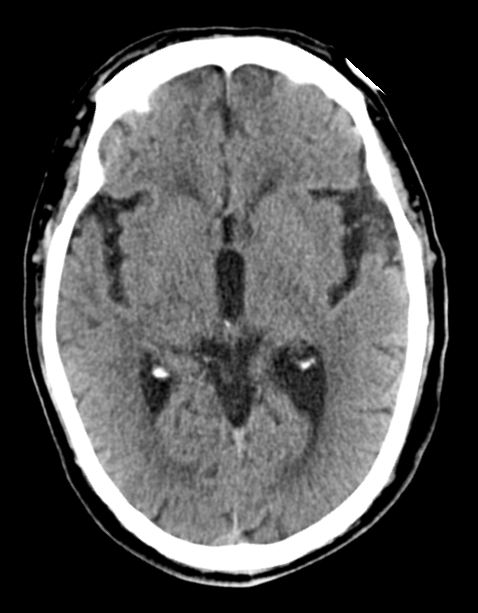

前文讲到脑卒中分为两大类(缺血性脑卒中和出血性脑卒中),两种卒中在临床表现上有很多相似之处,即使是专业人员仅仅通过临床表现也未必能准确鉴别。所以,怀疑脑卒中的患者应尽快进行头颅CT扫描以辨别是出血性脑卒中还是缺血性脑卒中。

脑出血的CT表现

缺血性脑卒中的CT表现